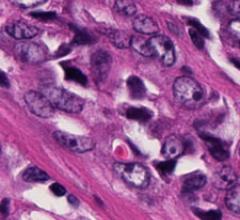

January 8, 2009 - A newly identified gene, called metadherin, might cause breast cancer tumors to spread and become resistant to chemotherapy, according to a study published in the journal Cancer Cell.